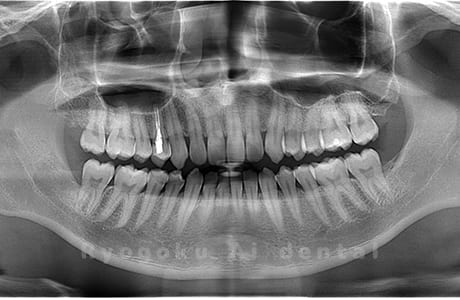

真っ直ぐ生えている親知らず

親知らずが真っ直ぐ生えているタイプです。

このタイプは真っ直ぐ生えていて咬み合わせに問題がなければ、抜歯しないケースもあります。ただし、虫歯になっていたり、痛みがあったり、咬み合わせが悪かったりすると抜歯をおすすめします。